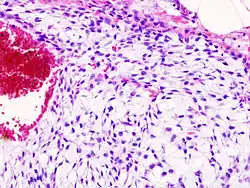

Histopathology